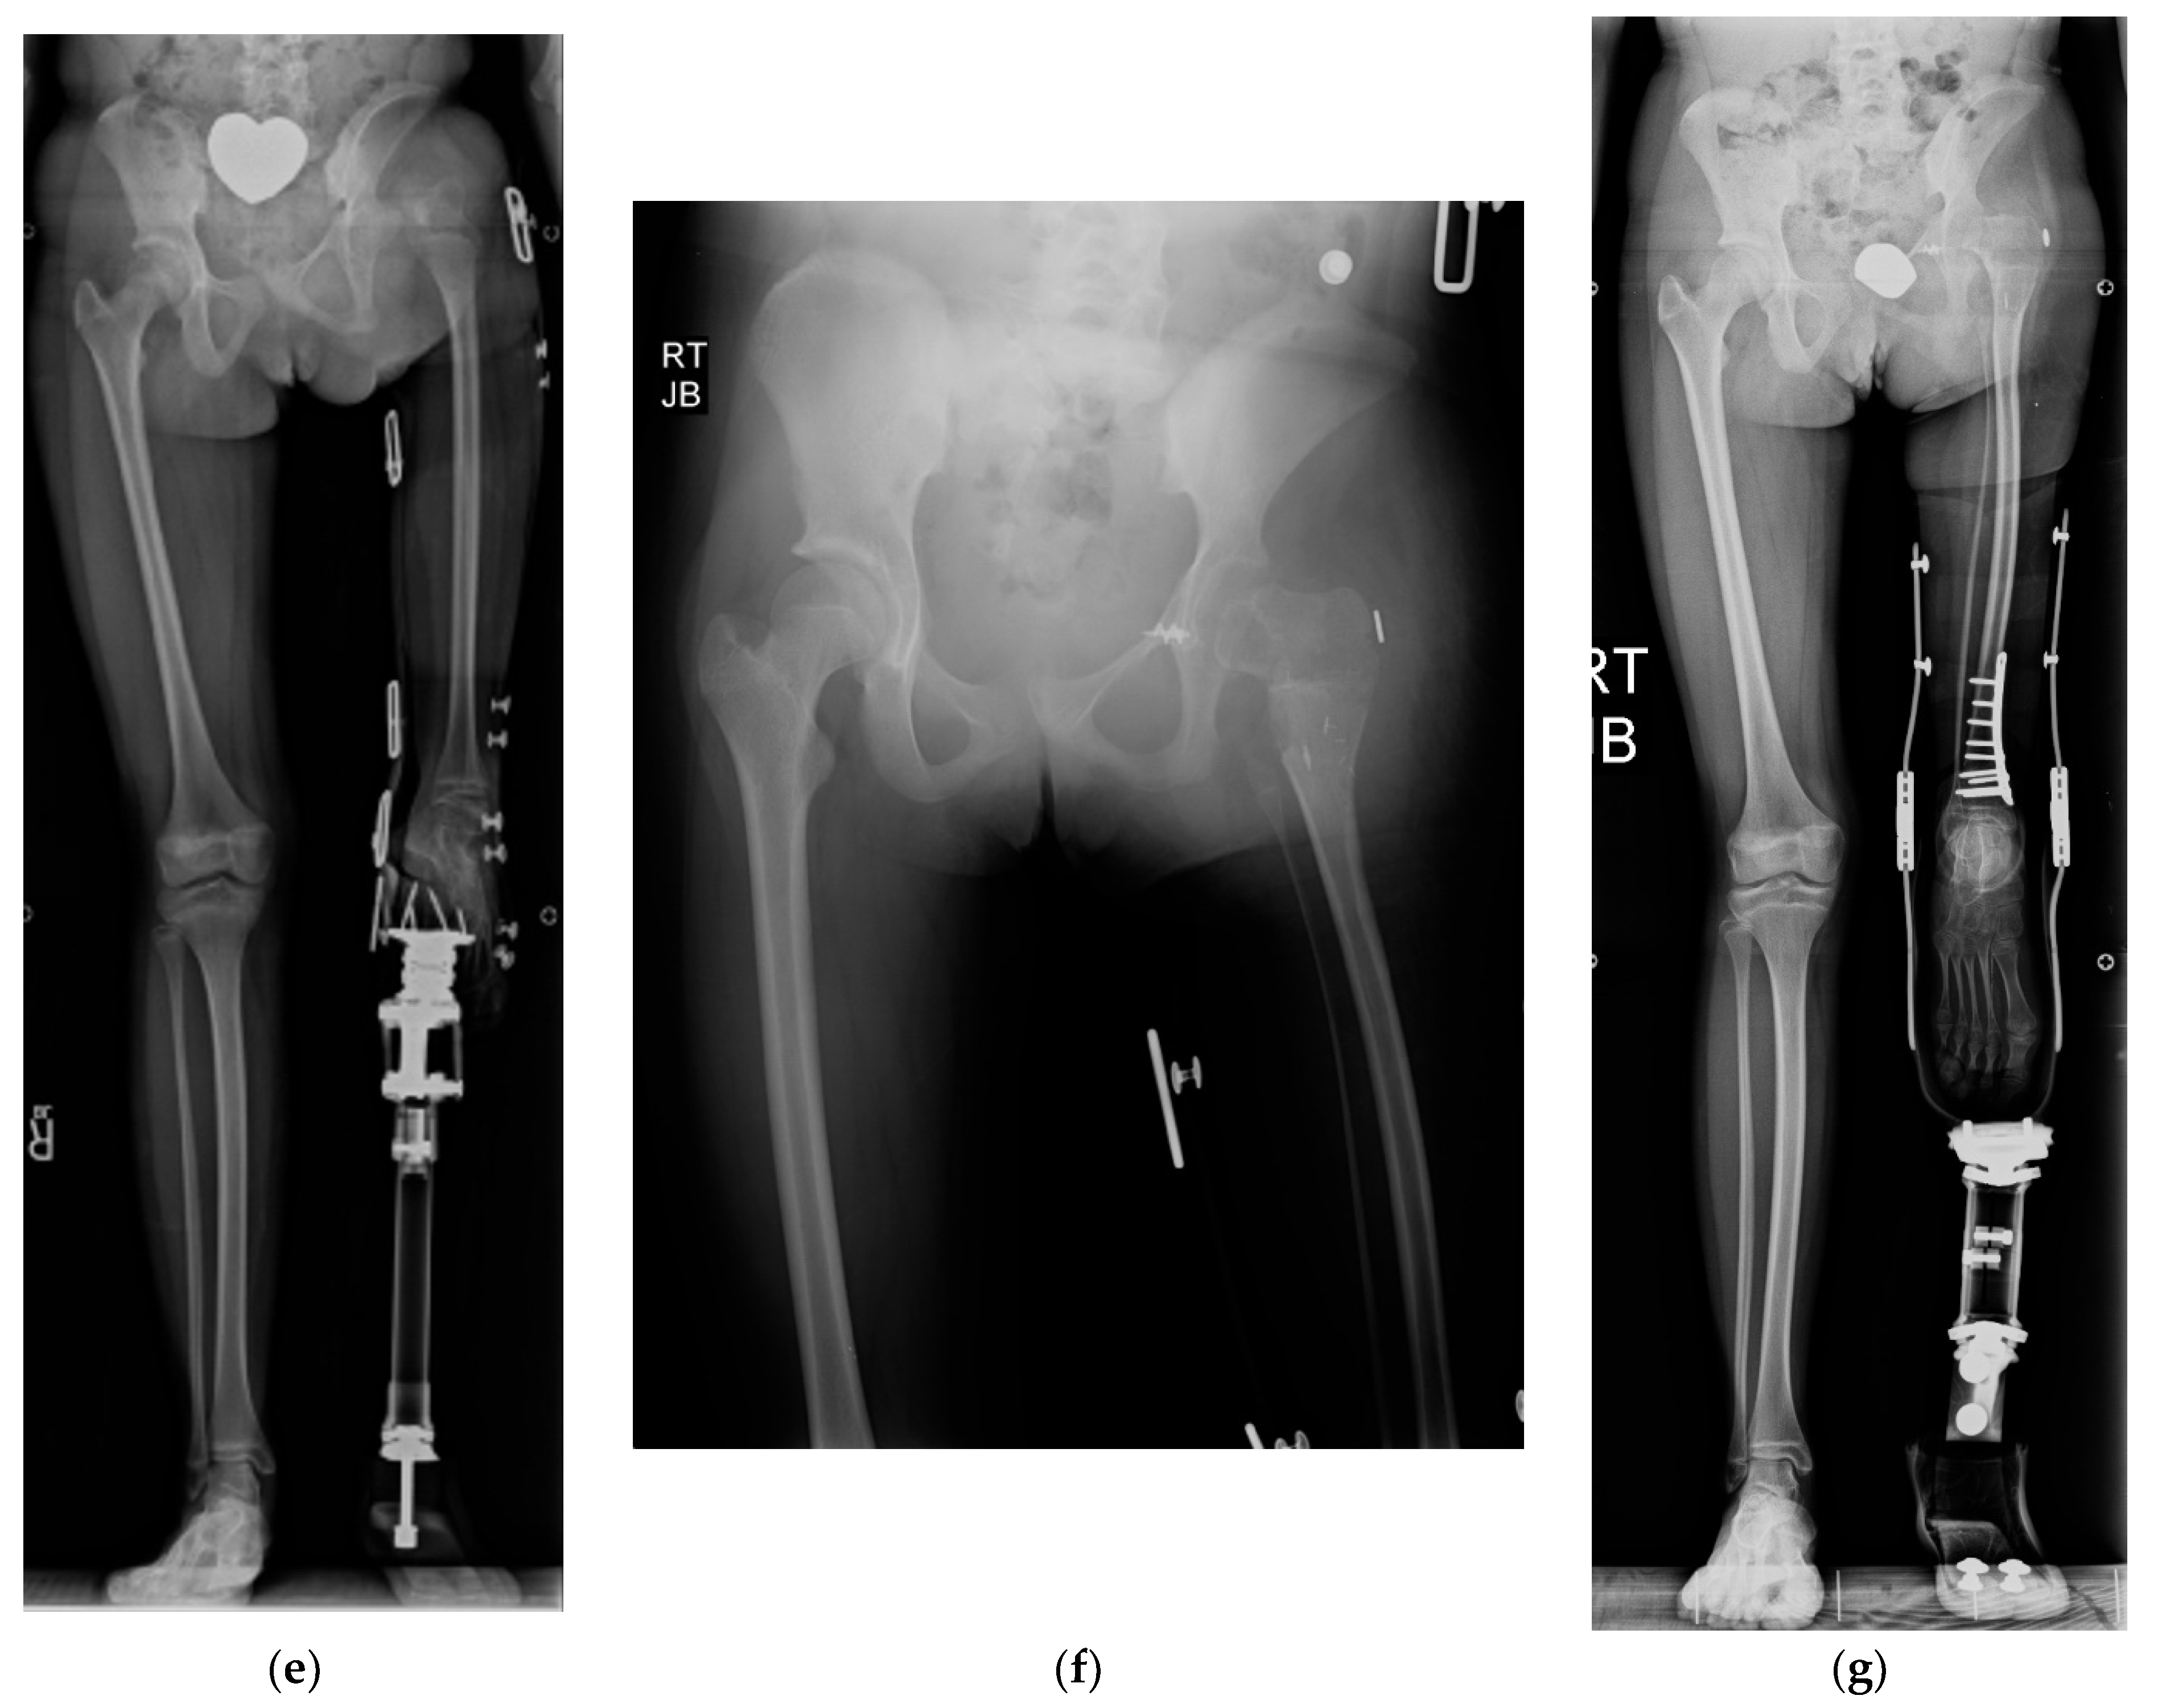

Figure 7.

(a) Illustration of CFD type 2c with congenital knee fusion with knee flexion deformity. The fibrous femoral neck anlage tethers the upper femur from migrating proximally. (b) Illustration showing the first step which is correction of knee flexion deformity with excision of distal femoral physis. (c) Illustration of the second step which is PaleySling–Van Nes rotationplasty. The rotationplasty is performed through the knee fusion site. The proximal femur is stabilized using the fascia lata by creating a sling around the proximal femur. The sling plus the fibrous neck anlage stabilize the upper femur from migrating proximally and while preserving the hip flexion-extension mobility (d) AP long radiograph (right) of a 14-year-old boy with bilateral CFD. The right side is classified as type 2c and also has a congenital knee fusion as seen on the long lateral radiograph (left). On the left side it is classified as a CFD type 3b and the knee joint is present and functional. (e) Standing long radiograph one year after bilateral rotationplasty performed in two separate surgeries. On the right side the rotationplasty was performed through the congenital knee fusion site together with a sling procedure at the hip (PaleySling–Van Nes). On the left side a Paley–Brown rotationplasty was performed together with a supramalleolar osteotomy for realignment.